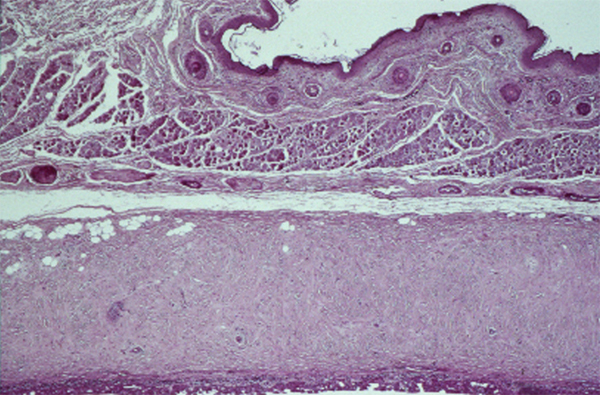

Fig. 1-6 Histologie de la cornée (hématoxyline–éosine [HE] × 5).

En contact avec le film lacrymal, l’épithélium cornéen de surface est de type pavimenteux stratifié. Il comporte de cinq à sept couches de cellules, mesure 50 μm d’épaisseur et représente 10 % de l’épaisseur totale cornéenne (fig. 1-6 et 1-7).

La cornée comprend cinq couches qui sont de dehors en dedans : l’épithélium pavimenteux au contact du film lacrymal reposant sur une membrane basale ; la couche de Bowman qui correspond à une condensation du stroma antérieur ; le stroma cornéen ; la membrane de Descemet ; les cellules endothéliales. La membrane de Descemet correspond à la membrane basale des cellules endothéliales.

La cornée comprend cinq couches qui sont de dehors en dedans : l’épithélium pavimenteux, la couche de Bowman qui correspond à une condensation du stroma antérieur, le stroma cornéen, la membrane de Descemet et les cellules endothéliales. La membrane de Descemet correspond à la membrane basale des cellules endothéliales. La cornée reçoit une riche innervation sensitive (plexus cornéen) à partir des nerfs ciliaires antérieurs de la branche ophtalmique du trijumeau.